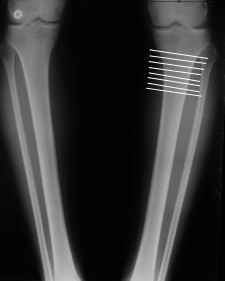

You can do the osteotomy in a "focal dome" or in a transverse fashion. The dome has the advantage of having a good contact, allowing weight bearing as tolerated early on.

The level is below the tibial tuberosity.

The frame I use is pretty simple, with one wire each in the proximal and distal ring, two schanz pins in the proximal ring, and one each in the middle and distal ring.

I preconstruct a frame with the proximal ring in varus by the use of coupled washers in the threaded rods in the front and back. These are used as hinges, and after the correction, a medial and lateral threaded rod is also added.

Since the center of rotation of these deformities is usually near the knee joint line, lateral translation of the distal fragment is necessary to normalise all the axes.

You can also do the osteotomy in a transverse fashion.

When I use an orthofix fixator, the osteotomy is oblique, starting below the tuberosity and ending 1 cm away from the lateral cortex at the level of the head of the fibula. No fibular osteotomy is needed there. The deformity is gradually corrected over 2 or three weeks.

You could also do the same with an ilizarov fixator

Посмотрел я картинки:(

Это не эстетика.

Это рубка леса и лучевая болезнь.

Very nice correction but, to my eye there is some 'over' correction of the tibia, now in some proximal valgus?

What is the hka?

What about the P/F joint orientation.